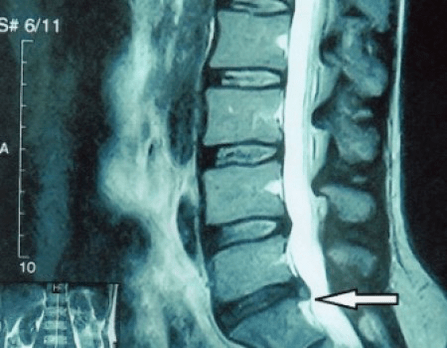

Étant donné que les disques eux-mêmes ne peuvent être vus qu'à l'aide de la tomodensitométrie ou de l'IRM, la tomodensitométrie par résonance magnétique et par rayons X est indiquée pour clarifier la structure interne du cartilage et des formations telles que les saillies et les hernies. Ainsi, à l'aide de ces méthodes, un diagnostic est posé avec précision et le résultat de la tomographie est une indication, voire un guide topique, pour le traitement chirurgical d'une hernie dans le service de neurochirurgie.

- si vous avez une hernie, vous devez la surveiller de manière dynamique, effectuer des IRM régulières, éviter d'augmenter sa taille ou effectuer un traitement chirurgical moderne mini-invasif, car sans exception, toutes les méthodes conservatrices de traitement de l'exacerbation de l'ostéochondrose laissent la hernie en place et n'éliminent que les symptômes temporaires : inflammation, douleur, tirs et spasmes musculaires.

Il est conseillé que chaque patient, après progression des symptômes, en présence de complications, subisse une IRM et consulte un neurochirurgien. Les opérations modernes mini-invasives permettent d'enlever en toute sécurité des hernies assez volumineuses, sans hospitalisation prolongée, sans être obligé de s'allonger pendant plusieurs jours, sans compromettre la qualité de vie, puisqu'elles sont réalisées à l'aide de la technologie moderne vidéo-endoscopique, radiofréquence, laser ou plasma froid. Vous pouvez évaporer une partie du noyau et réduire la pression, réduisant ainsi le risque de hernie. Et vous pouvez éliminer radicalement le défaut, c'est-à-dire en vous en débarrassant complètement.